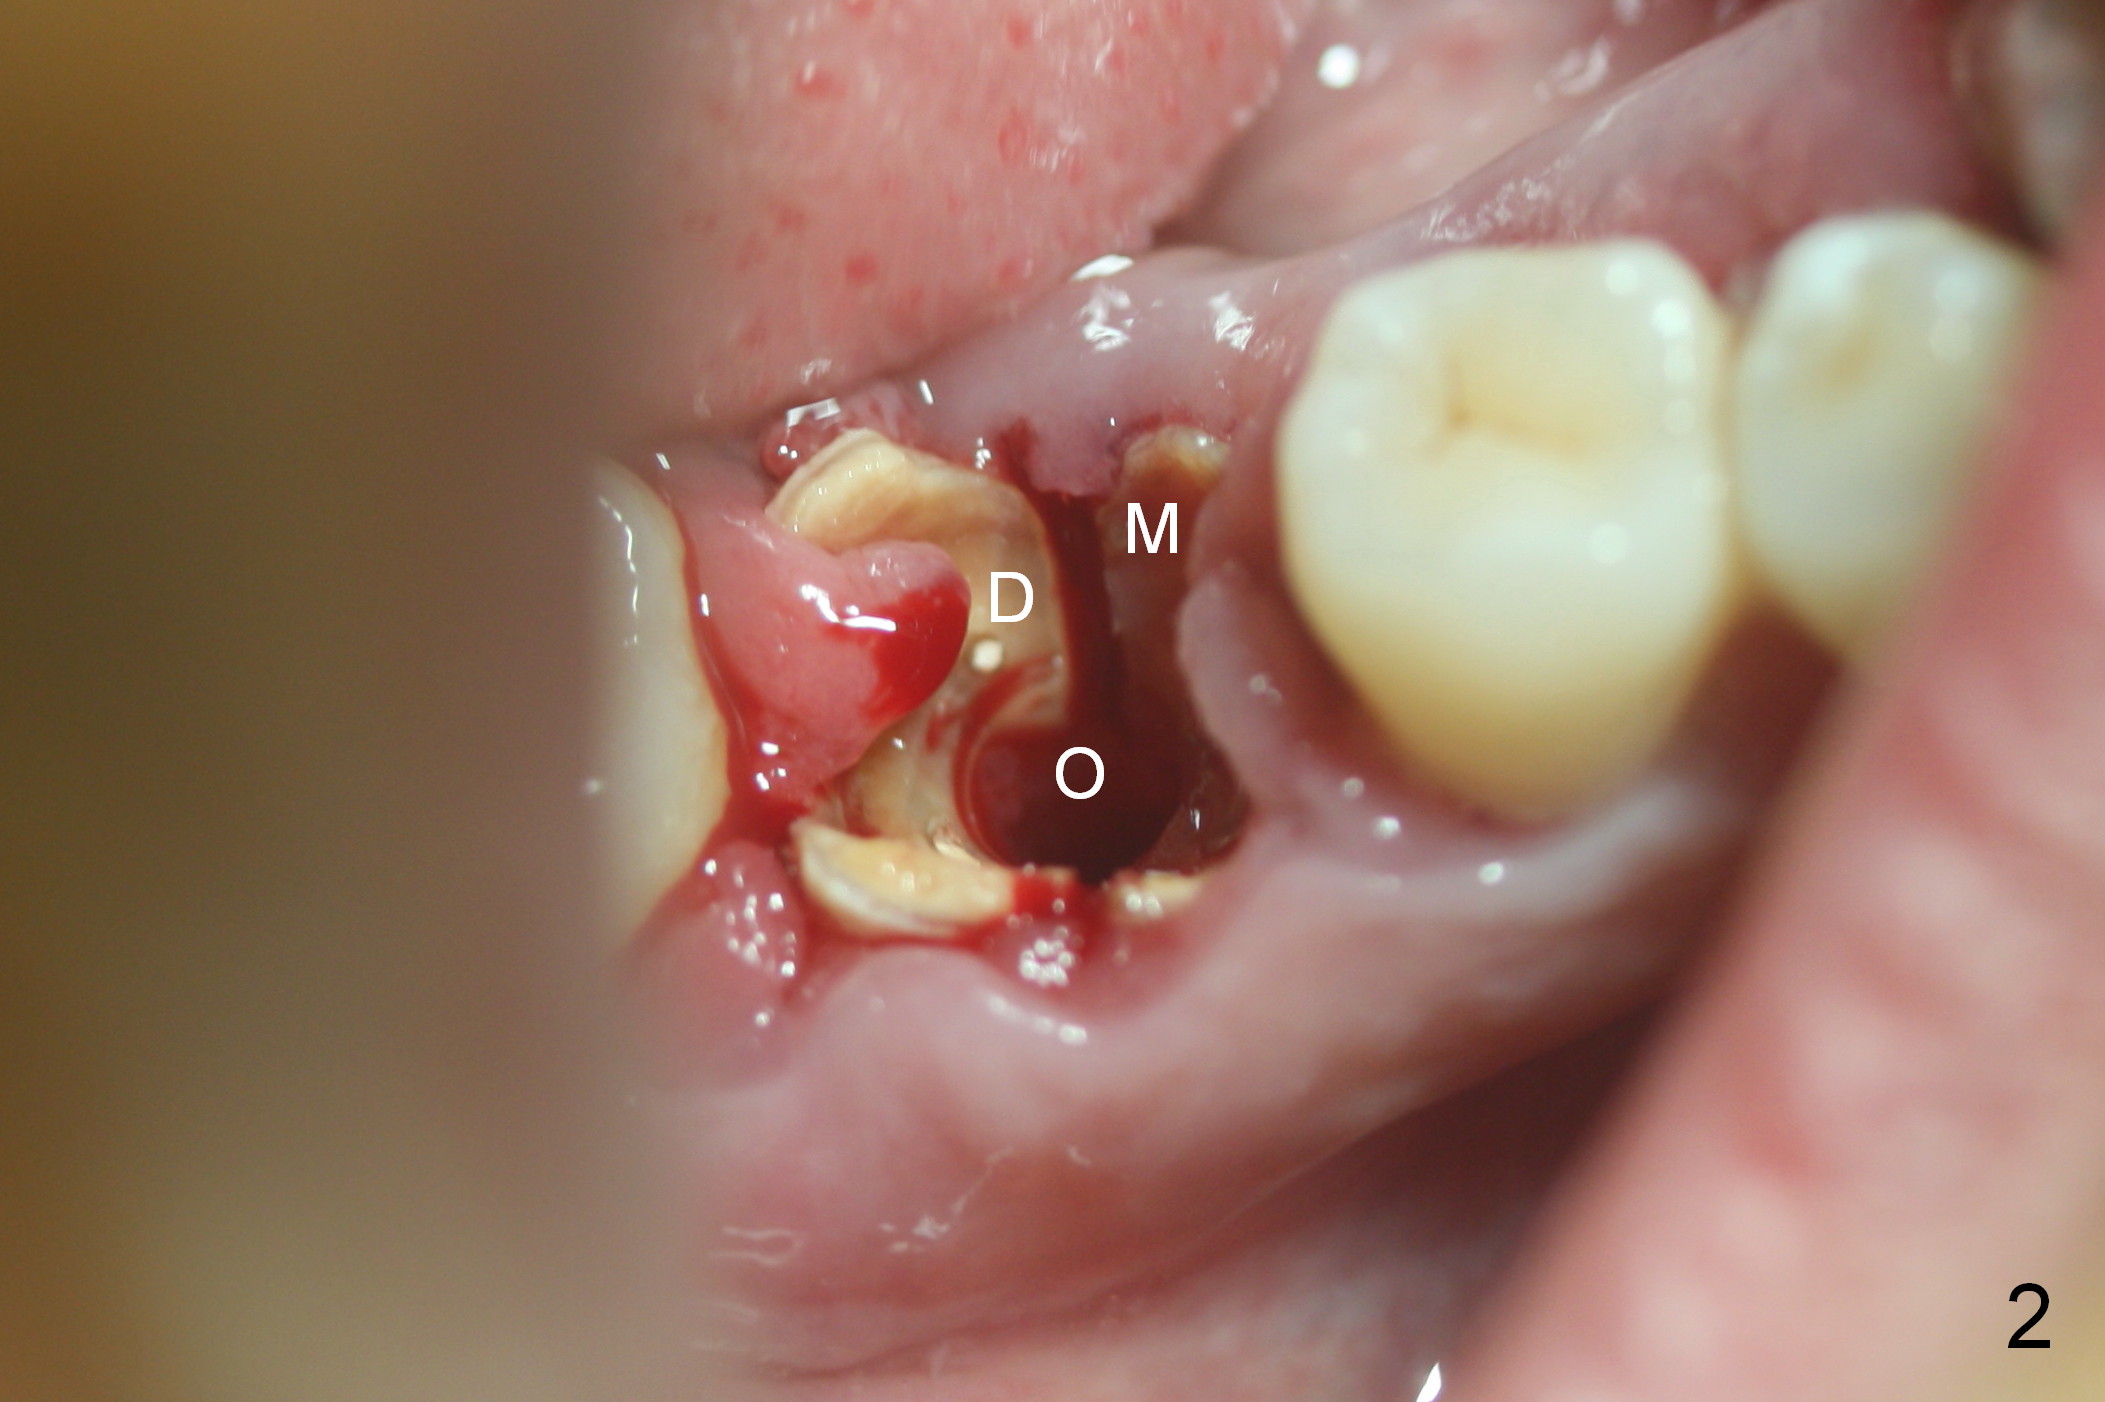

After cleaning the root surface with a surgical curette, a 1.6 mm pilot drill is used to start osteotomy (O) between the mesial (M) and distal (D) roots, followed by a marking bur and 3.8 mm Magic drill 13 mm deep (Fig.1,2). Following root removal, the 3.8 mm drill is reused for 11 mm (Fig.3). After deepening the osteotomy for another 2 mm, a 4.5x13 mm implant is placed with insertion torque of 50 Ncm, followed by allograft (*, .5-2 mm) and a 5x4(2) mm abutment (Fig.4,5). An immediate provisional is fabricated to close the socket (Fig.6 P (lock in)). The detached buccal gingiva (Fig.6 *) is kept in place by applying periodontal dressing (Fig.7 *). Red dashed lines in Fig.1, 3, 5 represents the superior border of the Inferior Alveolar Canal and Mental Foramen.